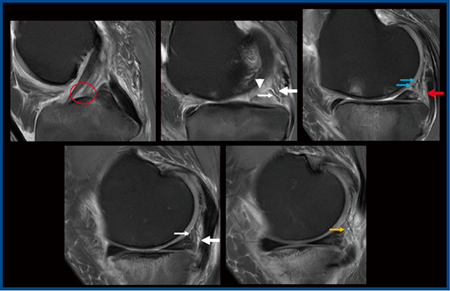

3.膝関節の評価

図5は交通外傷の症例で,これまでMR画像では評価できないとされてきた前十字靭帯遠位部の部分断裂(○)が明瞭に描出されている。また,内側半月板後角に断裂(図5 ▽)を認めるほか,後内側支持組織の損傷(←)が視認できる。斜膝窩靭帯(図5←)の腫脹を認めるものの,後斜走靭帯を構成するcapsular arm(→)とcentral arm(→)を同定することもできる。

このほか,PIQEを適用した膝蓋骨の関節軟骨のMR画像を拡大したところ,軟骨下骨,境界領域,関節軟骨の深層・中間層・表層が明瞭に描出され,病理所見をきれいに反映していた。さらに,損傷部においても,表層の欠損や深層の浮腫による信号上昇,軟骨下骨の信号変化が明瞭であった。

図5 PIQEによる交通外傷症例の膝関節損傷および靭帯断裂の描出